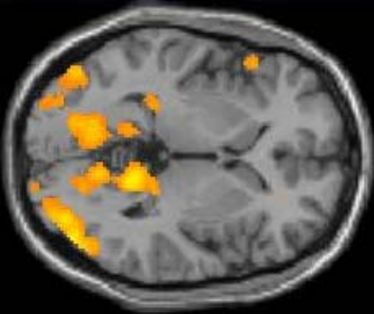

Probanden gesucht

Probanden gesucht